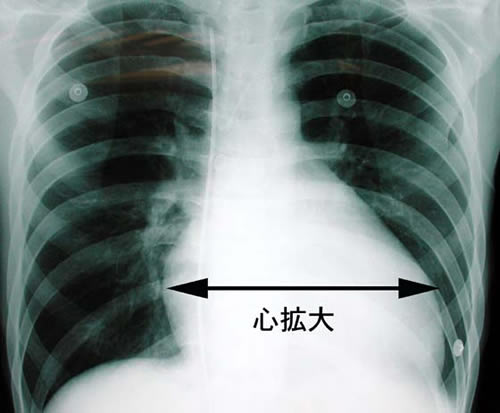

◆拡張型心筋症

そもそも 拡張型心筋症 は 心臓機能が著しく低下するもの

まずは レントゲン を撮影。

するとその写真を見た?先生がいきなり私を呼びました。

勿論順番ではありません。

・・・すみませんが 心臓 が大きいと言われて事は?

・・・毛が生えていると言われたことはありますけど、

・・・いや、冗談ではなく言われたことは無いですか?

・・・何度もレントゲン取っていますが初めてです。

と言う会話のあと、先生は真剣な顔をして

先生はもう一度レントゲンを眺めて

・・・残念ですが私の病院では 手に負えない 病気の可能性が